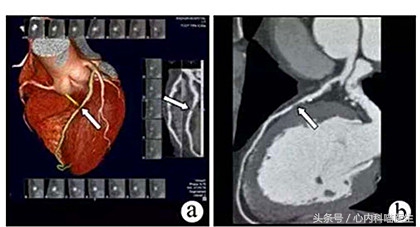

老张男性,今年62岁,2年前因心绞痛发作,住院治疗,造影检查发现:前降支血管中段有一处严重狭窄。这是造成心绞痛发作的元凶!但是该处狭窄却位于血管分叉和心肌桥之间,不适合支架治疗。只好选择保守药物治疗。

老张非常听从医生的嘱托,坚持口服药物治疗,前几天复查造影显示:2年前的那处血管狭窄,不但没有进一步加重,反而减轻,血管腔更加通畅。